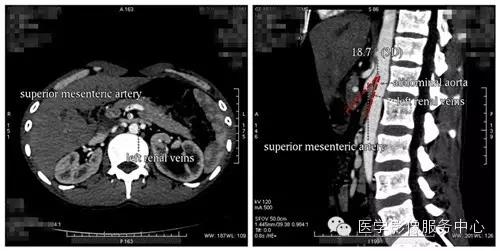

NCS典型的CT表现包括:(1)左肾静脉在穿过腹主动脉和肠系膜上动脉夹角时受压、明显变窄,受压部近端扩张,呈“鸟嘴征”;(2)肠系膜上动脉与腹主动脉夹角变小(小于35°有诊断意义);(3)可同时伴发十二指肠瘀滞、男性精索静脉曲张、女性盆腔静脉曲张。

人体的血管像四通八达的道路一样,是有一定走向的。左肾静脉行走在腹主动脉和肠系膜上动脉之间,这两条动脉构成40~60度的夹角,左肾静脉刚好通过此夹角。从解剖上看,右肾静脉径直注入下腔静脉,行程短而直。而左肾静脉则需穿过腹主动脉和肠系膜上动脉之间的夹角,跨越腹主动脉前方始能注入下腔静脉,因此左肾静脉远较右肾静脉长。正常时,肠系膜上动脉与腹主动脉之间的夹角被肠系膜、脂肪、淋巴结和腹膜等所充塞,使左肾静脉不致受到压挤。当青春期发育较快、身高迅速增长、脊柱过度伸展、体形急剧变化或肾下垂等情况下,左肾静脉在这个夹角中的日子就不好过了,会受到挤压,引起血流变化和相应的临床症状。 医学百科网 | YxBaike.Com

根据左肾静脉的解剖位置可将NCS分为前、后两型。前型NCS是指左肾静脉从腹主动脉和肠系膜上动脉之间穿过,并受到压迫,此型最为常见。后型NCS是指左肾静脉从腹主动脉和脊柱之间穿过,并受压于腹主动脉和椎体。